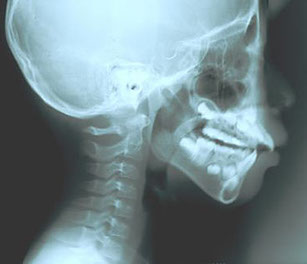

Adenoids - before and after

Cephalogram before and after using Patakara

Solid lines: Before using Patakara

Dotted lines: After using Patakara for 20 months

After: after 20 months of Patakara facial therapy. Symptons were alleviated due to corrected respiration (nasal).

After using for 20 months, changes in the cervical lines and facial bones can be seen clearly from the X-ray.